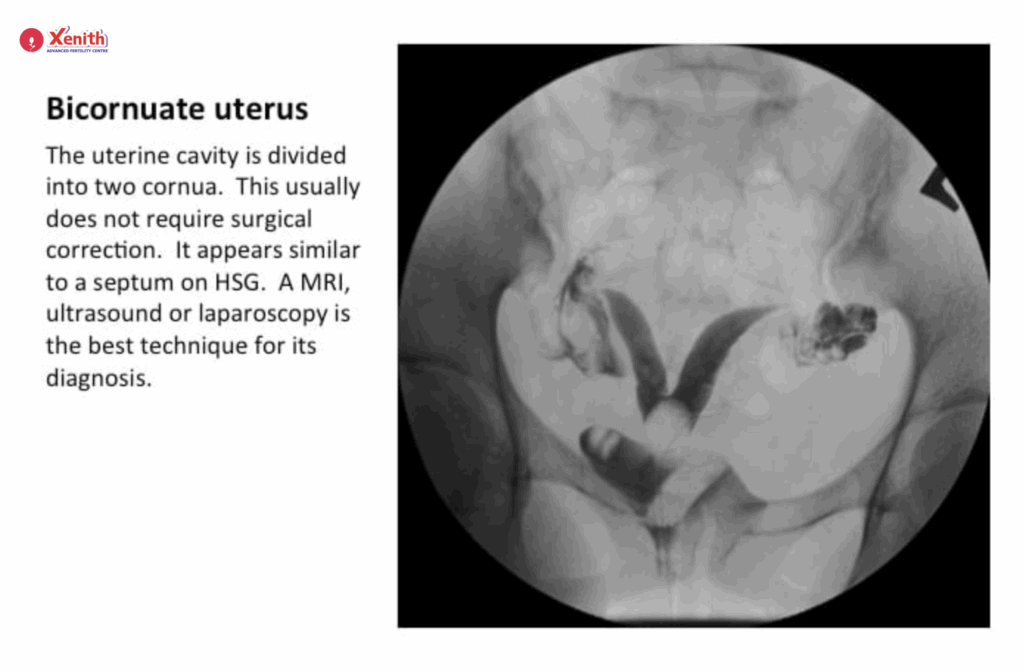

Congenital Uterine Abnormalities: Such as a septate uterus or bicornuate uterus, which can affect fertility or cause recurrent miscarriages.

Hysterosalpingography (HSG) is a medical imaging procedure used to assess the shape and structure of the uterus and to check whether the fallopian tubes are open or blocked. These two factors are key to natural conception — because for pregnancy to occur, the egg and sperm need to meet in an open fallopian tube.

During the procedure, a contrast dye (a special liquid visible under X-ray) is gently introduced through the cervix into the uterus and fallopian tubes. As the dye flows through, a series of X-ray images are taken. These images allow your doctor to see the outline of the uterus and tubes and detect any abnormalities such as blockages, adhesions, or structural issues.